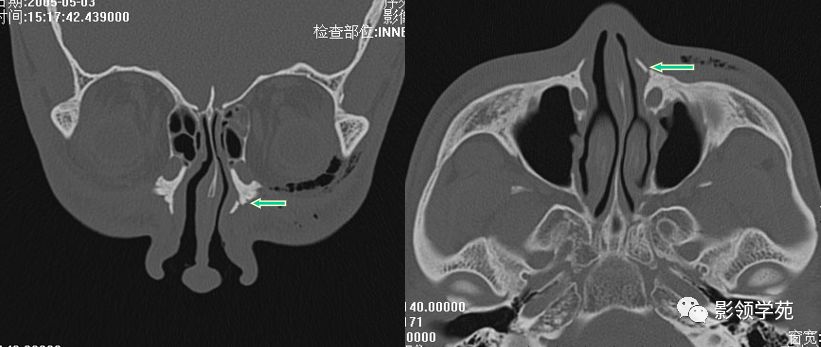

骨折HRCT表现

- 外形

- 骨折线

- 软组织肿胀、积气

- 邻近部位骨折

右侧鼻骨骨折

左上颌骨额突骨折

双侧鼻骨骨折

双侧上颌骨额突骨折